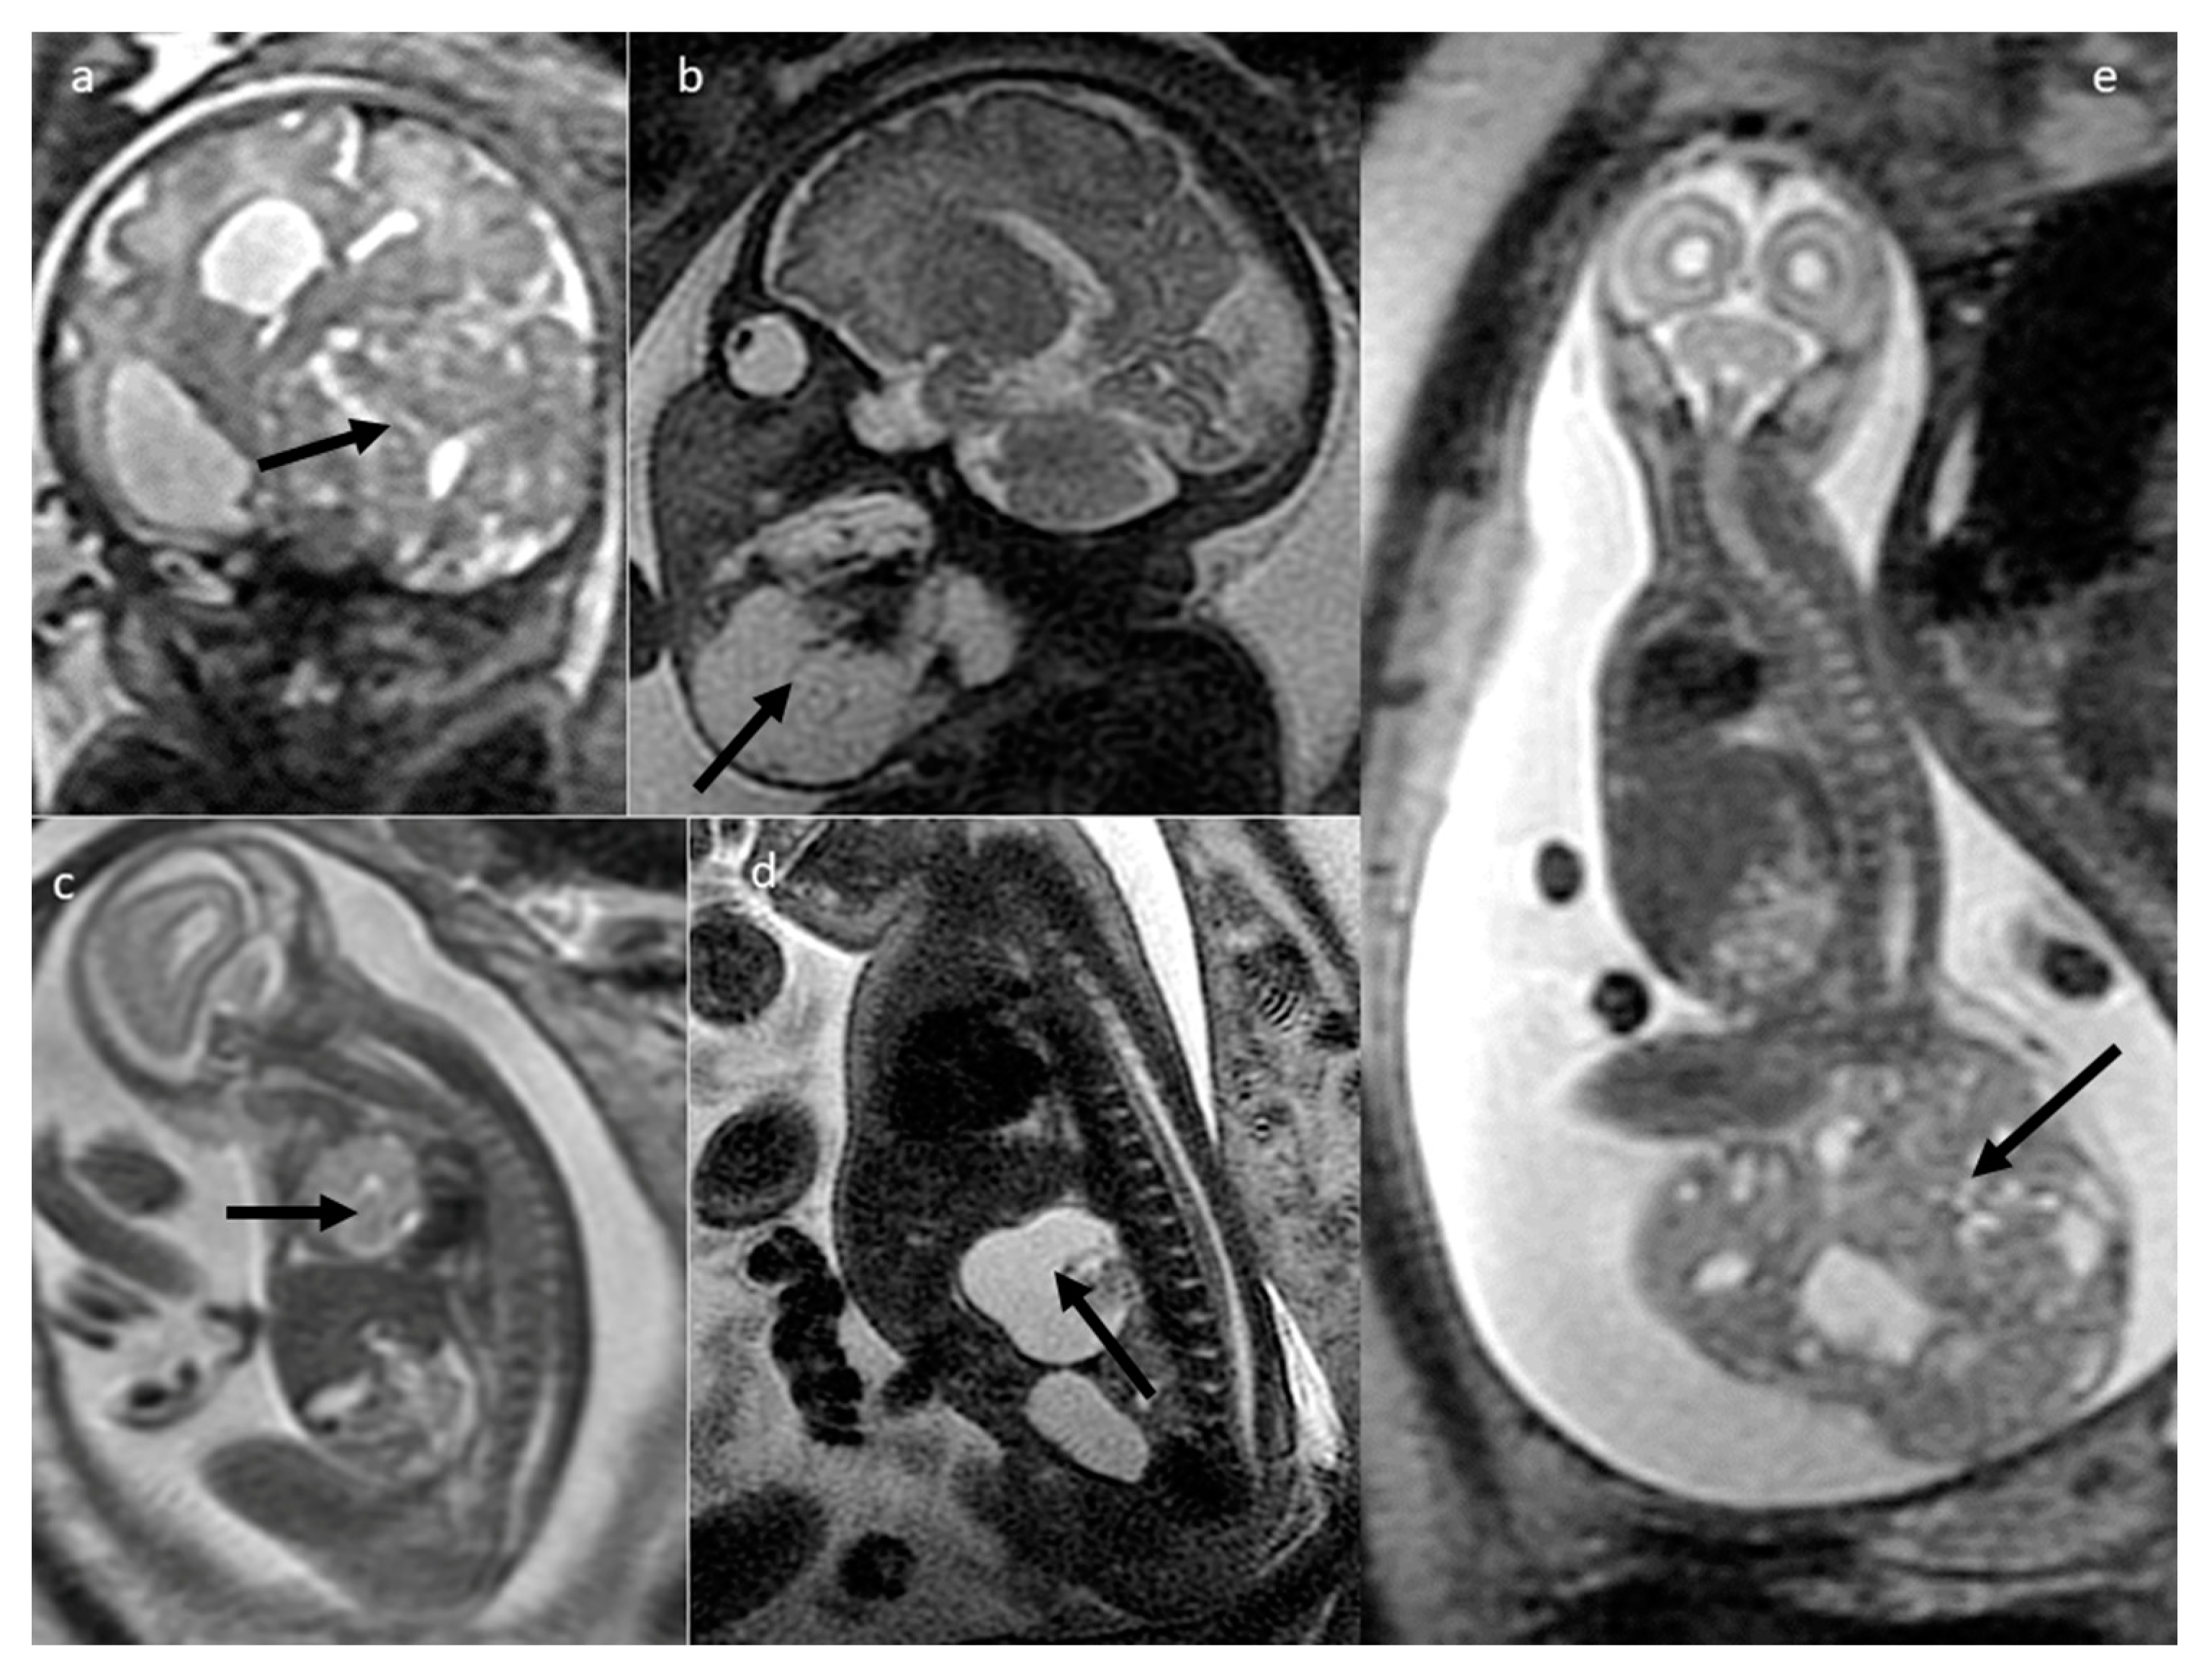

| Teratoma | sacrococcygeal | 25 | 268 [2.5–1145.165] | yes (13/17) [918–1661) | cystic (6) mixed (19) | yes 8/13 | yes (3/4) |

| head and neck | 13 | 176.1 [1.78–877.11] | yes (9/13) (796–1294) | solid (3) mixed (8) cystic (2) | yes (8/13) | yes (1) | |

| thorax and abdomen | 8 | 32 [1.49–134.98] | yes (3/6) | mixed (3) solid (3) cystic (2) | yes (4/5) | yes (1) | |